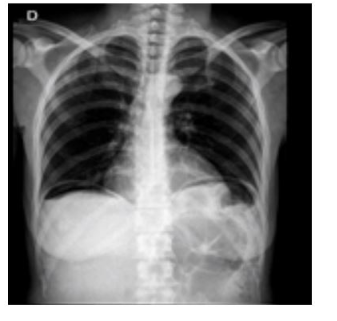

Um homem de 45 anos, sem antecedentes médicos relevantes, refere dor abdominal de início súbito há cerca de 12 horas. A dor foi piorando, sendo acompanhada de náuseas e vômitos. Nega febre ou alteração da urina ou do hábito intestinal. É tabagista e etilista. Refere uso de anti-inflamatório por dor nas costas, nos últimos 15 dias. Está descorado +/4+. PA: 100 × 60 mmHg; FC: 110 bpm. O abdome é rígido, com DB +. Feita a radiografia ilustrada a seguir. (VER IMAGEM) Principal hipótese diagnóstica e melhor conduta: